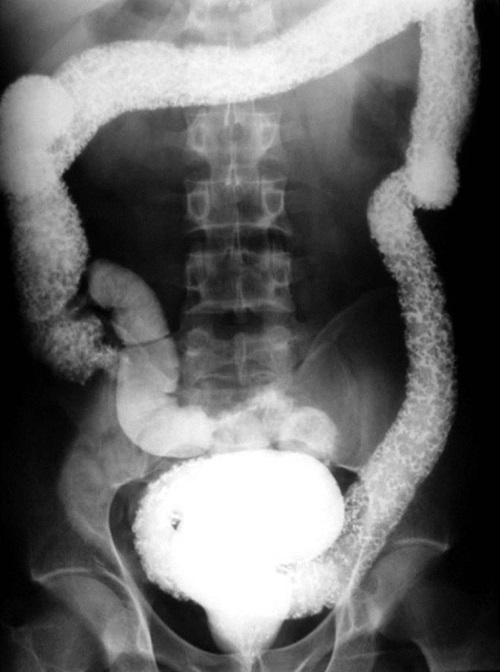

Barium study is shown from a patient with worsening Crohn’s disease. Long segment of narrowed terminal ileum in a ‘string like’ configuration in keeping with a long stricture segment. Termed ‘Kantor’s string sign’.